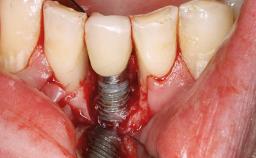

A 65-year-old female patient was referred to the periodontist for assessment and management of implant site 12. Implant 12 had been placed ten years previously and restored with a cemented single crown. The patient was a non-smoker in good general and periodontal health. On examination there were 7 mm probing depths at implant 12 with suppuration and bleeding on probing. The patient was aware of the presence of pus but had no discomfort. A periapical radiograph showed marginal bone loss to approximately the third thread of the implant. Previous radiographs obtained from the referring clinician indicated that there had been progressive bone loss since the implant was restored. A diagnosis of periimplantitis was made.